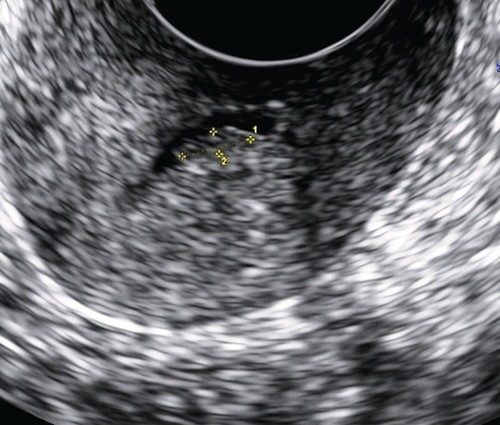

Отчасти это связано с тем, что для всех вариантов полипов шейки матки характерны небольшие размеры и одиночность поражения. К тому же, например, железистые полипы вообще не видны при ультразвуковом сканировании из-за того, что не только эхонегативная ткань железистых полипов сливается с изображением миометрия шейки матки и может быть неотличима от Ov. Nabotii (рис. 1), находящихся рядом с эндоцервиксом, но и из-за слизи в просвете шеечного канала.

Рис. 1. Парацервикальные кисты с содержимым различной эхоструктуры.